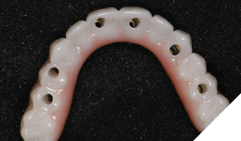

The patient returned 2 weeks from the impressioning appointment for a prototype try in. At this appointment the esthetics, phonetics, soft tissue approximation and occlusion were confirmed. There was no requirement for a verification jig due to the accuracy of the Nexus solution. The restorations were manufactured with milled gold anodized titanium bars overlaid with monolithic zirconia (Figs. 24A-C, 25A-C).

Fig. 24A

Fig. 24B

Fig. 24C